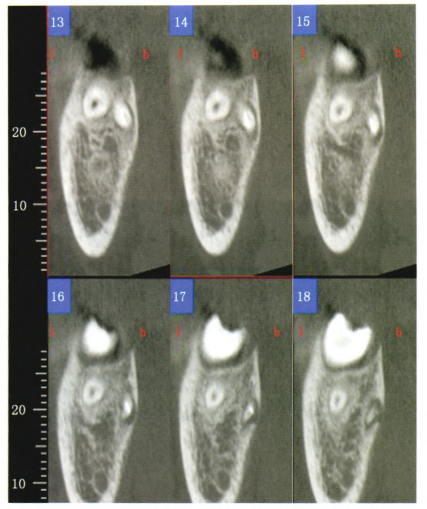

随后进行锥形束CT检查发现患者右颌下区及颏下区软组织内出现局限性蜂窝状透影区(见图3);

右下第一恒磨牙远中舌根根尖1/3向颊侧弯曲,角度较大(接近90°);弯曲处相应舌侧骨板缺如(见图4、5)。